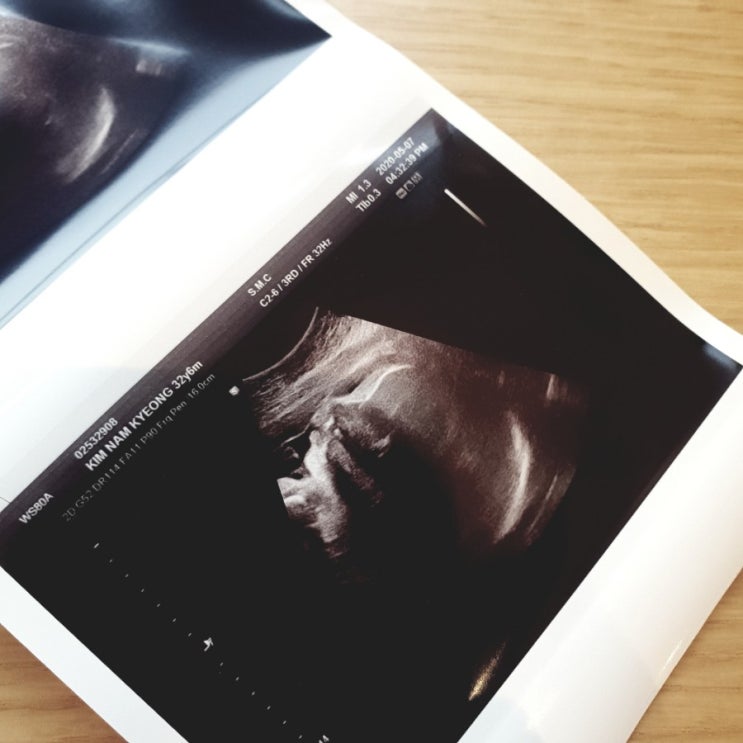

6월 24일 3.46kg 햇살이 탄생 ☀️ 초음파 볼때도 눈을 잘 뜨고 있어서 신기했는데 아니나 다를까 태어나자...

임신일기) 강북삼성병원 분만실. 37주 6일 양수터져서 입원했어요!

초기 피고임 없는 혈때문에 눕눕 그리고 건강했지만 코로나 땜시 집콕했던 중기를 지나 한 30주 부터는 하...

33주 정기검진 (소변검사)

30주가 넘으니 2주 마다 정기검진을 다니는데요 33주에는 소변검사만 하고 진료를 봤어요. 으아 근데 충격...

강북삼성병원 산부인과 /대학병원 산부인과 31주 정기검진 : 소변 채혈검사

12주 16주 20주 24주 29주 4주간 간격으로 다니다 30주부터 2주 간격으로 줄어듭니다. 떨령 31주는 소변검...